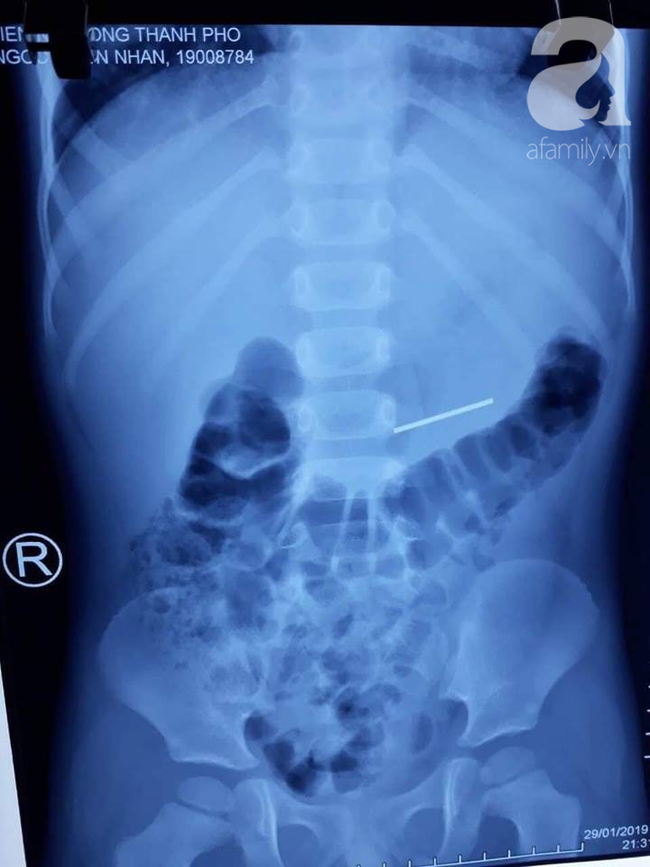

Trường hợp thứ hai là của một bé trai 4 tuổi (quê Long An). Khi đang nằm ngậm thanh cầu bánh xe đồ chơi, bé bất ngờ nuốt trôi luôn thanh dị vật dài 3 cm, có 2 đầu nhọn vào dạ dày gây thủng ruột phải đi cấp cứu.

Ảnh chụp X-quang cho thấy rõ dị vật trong người bệnh nhân.